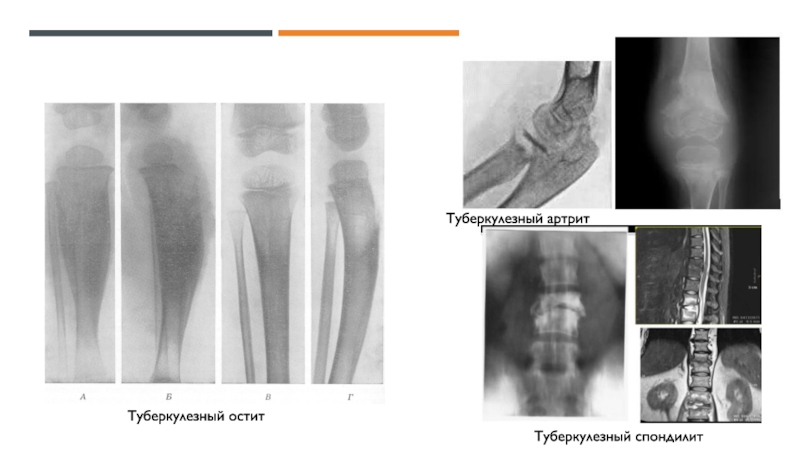

Федерации выявляется от 120 до 150 детей, впервые заболевших туберкулезом

костей и суставов, включая костные осложнения противотуберкулезной вакцинацииОколо 25% костных поражений у детей являются одной из локализаций генерализованного туберкулеза, 75% протекает в виде изолированных поражений скелета.

Чаще болеют дети раннего и дошкольного возраста